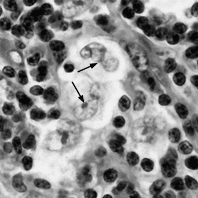

HLの組織像は様々な炎症性背景に数の少ない、大型の特異細胞が散見されるのが基本像である。新WHO分類では典型的なHRS細胞の出現するclassical HL(CHL)とpopcorn細胞の出現するnodular lymphocyte predominance HL(NLPHL)とに大別され、CHLはさらにlymphocyte rich (LR), mixed cellularity (MC),nodular sclerosis (NS),lymphocyte depletion(LD)の4型に細分される。H/RS細胞は小リンパ球より大きい光輝性核小体がみられ、その周りに明庭を有する大きな核をもつ細胞で、単核のものをH(Hodgkin)細胞、2核以上のものをRS(Reed-Sternberg)細胞という(図1,2,3)。多分葉の核をもつ細胞をpopcorn細胞と言う(図4)。

図2.Hodgkin細胞の電顕像 3000倍

細胞膜は平坦で、大型の核小体(矢印)を有する核(N)を認める。細胞質内には円形〜楕円形のミトコンドリアとひも状の粗面小胞体を散見する。